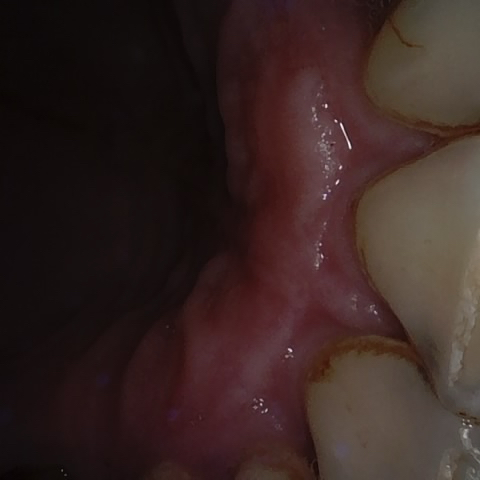

Annotated as "Good"